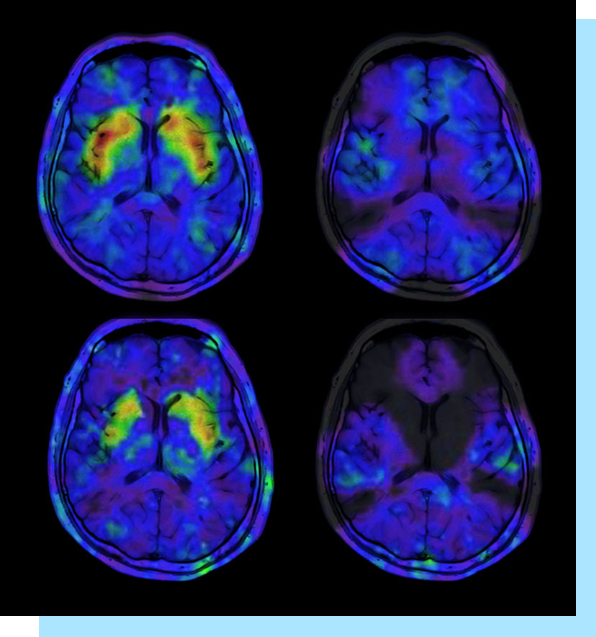

Los estimulantes como la metanfetamina funcionan diciéndole al cerebro que suelte mucha dopamina, un químico que puede hacerte sentir feliz a corto plazo. Pero con el tiempo, la metanfetamina puede agotar el cerebro en áreas importantes que te hacen sentir bien, lo que con el tiempo resulta en depresión y mal humor. La metanfetamina también puede causar problemas cardíacos inmediatamente y otros problemas de salud a través de sus efectos estimulantes en el cuerpo y estos pueden poner en peligro tu vida.

De todas las drogas recreativas, la metanfetamina eleva la dopamina y cómo se siente la persona a los niveles más altos y a los más bajos. Es por esto que se considera una de las drogas más adictivas.